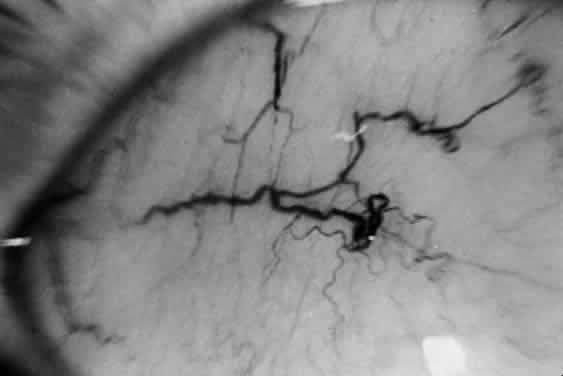

Ophthalmologic manifestations are an important feature of Tay-Sachs disease. Macular cherry-red spots develop in virtually all cases (Fig. 5). As a rule, the macular sign is evident by the time other neurologic signs appear in infancy. Clinically, this appears as a bright to dull red spot surrounded by a well-defined hazy gray, creamy white, or yellowish halo. The halo is the result of loss of transparency of the multilayered ganglion cell ring of the macula. The red spot is the normal blush of the more transparent central region of the macula, its color accentuated by the creamy halo surrounding it. The so-called cherry-red spot is the focal ophthalmoscopically visible sign of generalized retinal involvement in this disease.

Fig. 5. Characteristic cherry-red spot in child with Tay-Sachs disease.